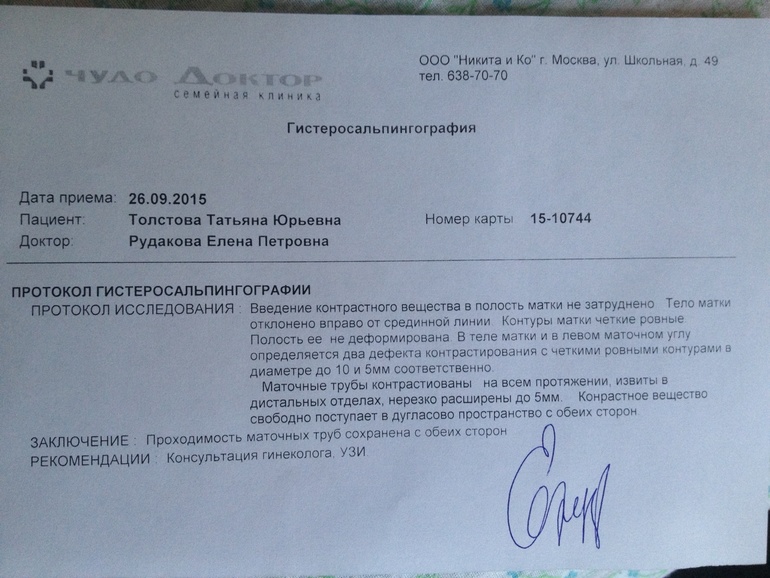

Медицинские снимки: Проходимость маточных труб

.jpg)

Раздел: Кадры-подсказки